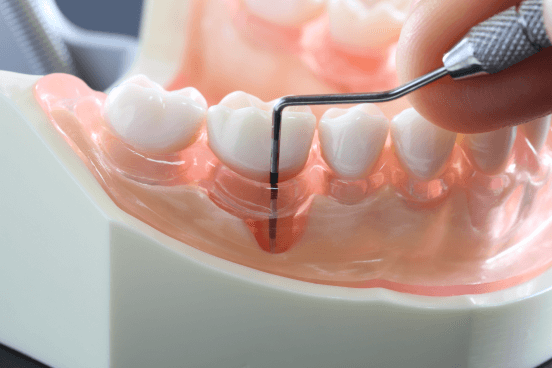

• 虫歯治療

虫歯治療

ごく初期の虫歯の場合は、進行を防ぐ適切な処置を施すことで、虫歯を削ることなく治すことが可能です。ただし、この段階での自覚症状がほとんどないため、歯科医院で定期的な検診を受けることで早期発見・早期治療、虫歯の予防に繋がります。日頃から虫歯にならない口内環境を整えていきましょう。